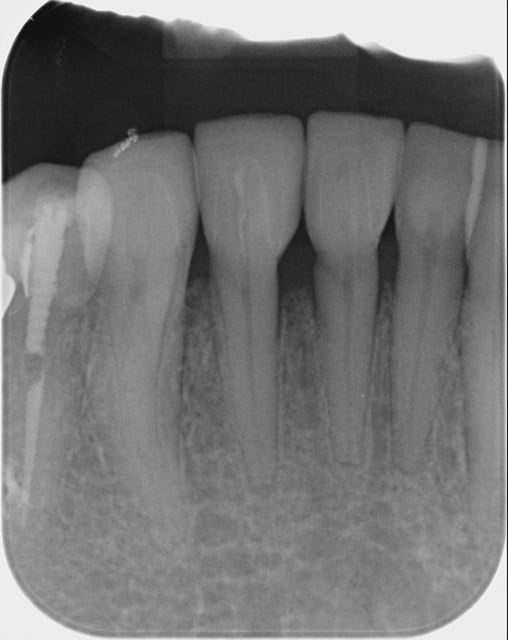

tient un boulot ou il y a un peu de tout.

bridge antérieur , car la pose d'implants nécessitait de la reconstruction trop importante, endo couronne sur les molaires mandibulaires par manque de hauteur, onlay. implants à la mandibule.

A noter les 2 PM maxillaires qui comportaient

chacune 3 canaux.